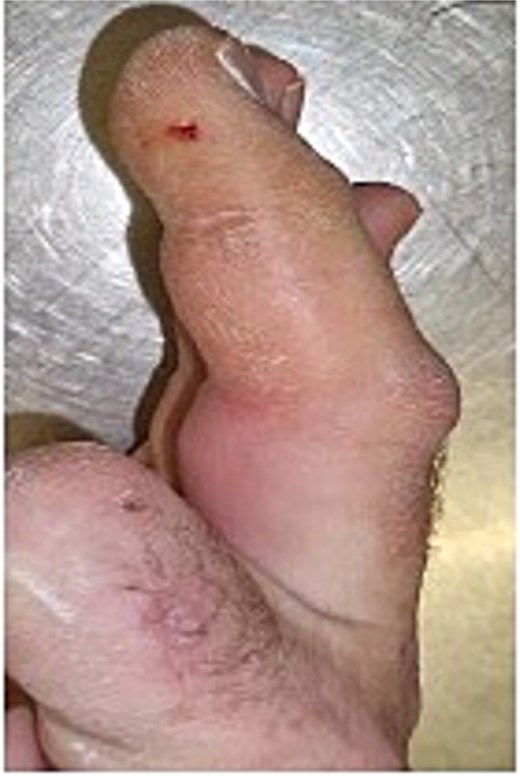

Initial presentation (Fig. 7) with accompanying X-ray (Fig. 8). Final image shows patients digit when he represented 2 months after original insult with a swollen finger and pus exudate (Fig. 9).

Image of patient three, showing his digit at presentation displaying small puncture wound on volar surface.

Patients three’s digit when he represented 2 months after original insult with a swollen finger in a flexed position and pus exudate.